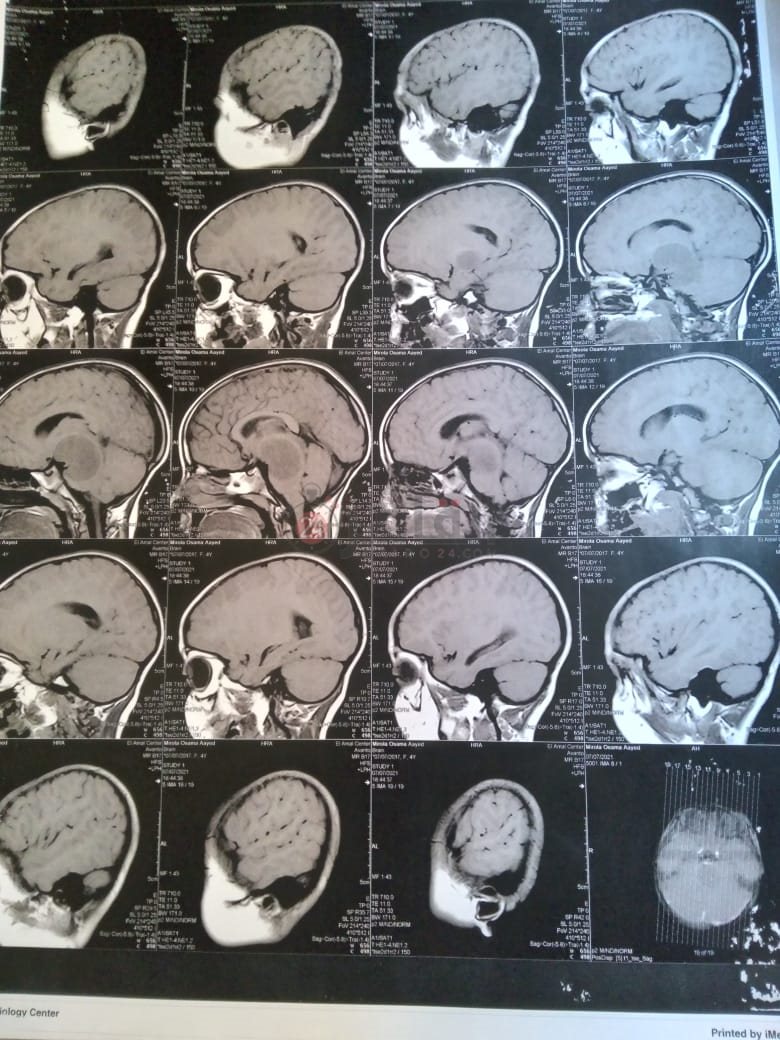

وأضاف: "أجرينا أشعة مقطعية لها لم يظهر بها أي شيء، ثم طلب الطبيب إجراء أشعة رنين على المخ، وهنا تبين وجود بؤرة سرطانية بالمخ، مشيرًا إلى أن:" الدكتور طلب مني أذهب إليه لوحدي من غير الأم والبنت، وقالي إن في ورم بس مش عارفين نوعه خبيث ولا حميد".

وأوضح أن حالة نجلته تتدهور بسرعة كبيرة، حيث أصُيبت حاليًا بشلل نصفي بالجانب الأيمن، لأن البؤرة حجمها 2.5 سم في 4.5 سم، ومرتكزة على جانبها الأيمن، مشددًا على أنها الحالة الأولى في العائلة التي تصاب بهذا المرض.